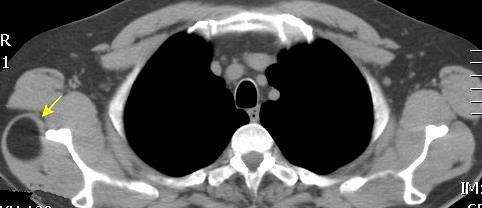

48 MASAS. LIPOMA SUBPECTORAL

Densidad similar al músculo con estriaciones internas de grasa

Hallazgo incidental . Región infraescapular 2% de TC del tórax. Bilateral 60%.

Burt AM et al. Imaging review of lipomatous musculoskeletal lesions. SICOT J2017/ Murphey MD et al. From the archives of the AFIP: benign musculoskeletal lipomatous lesions. Radiographics. 2004

Isointenso con grasa subcutánea